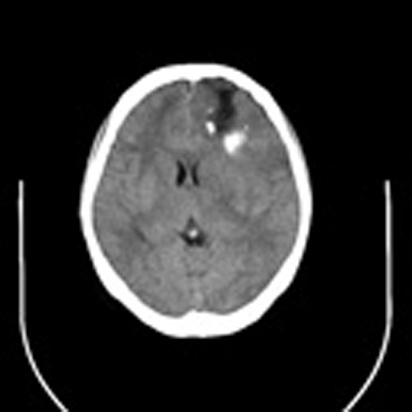

标题: CT16829:女,36,近20天偶有口眼歪斜短暂发作史,近日头痛。 [打印本页]

标题: CT16829:女,36,近20天偶有口眼歪斜短暂发作史,近日头痛。

近20天偶有口眼歪斜短暂发作史,近日头痛。患者先做ct发现病变后又做了mri检查,前日上传2次ct图像均未成功,今日补上。

少支胶质细胞瘤,胼胝体受累

大脑中线部位肿瘤向两侧生长,可见明显钙化影,考虑少枝胶质瘤,建议增强除外脑膜瘤

左额混杂密度肿块,经胼胝体跨越中线向右额叶生长,多考虑少支胶质细胞瘤,建议mr增强扫描,待排除血管畸形。

3-4级星形细胞瘤,对侧及胼胝体受侵